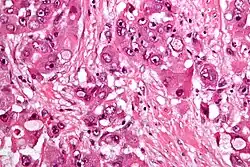

| Micrograph of fibrolamellar hepatocarcinoma showing the characteristic laminated fibrosis between the tumor cells with a low NC ratio. H&E stain. | |

The histopathology of FLC is characterized by laminated fibrous layers, interspersed between the tumor cells. Cytologically, the tumor cells have a low nuclear to cytoplasmic ratio with abundant eosinophilic cytoplasm.[1] Tumors are non-encapsulated, but well circumscribed, when compared to conventional HCC (which typically has an invasive border).